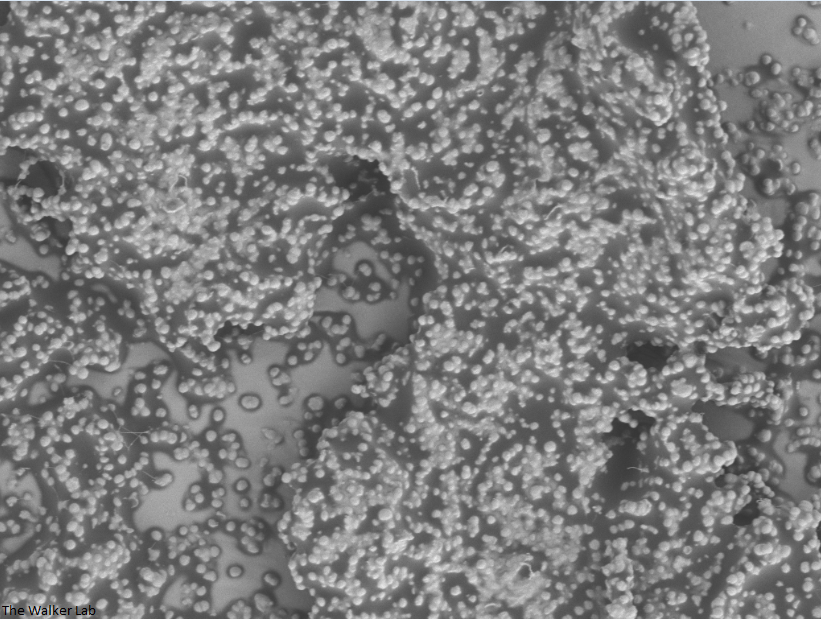

SEM Images of Mouse Catheters

Silicone urinary catheters have smooth surfaces, while latex urinary catheter surfaces are rough. Regardless of the catheter material, deposition of host inflammatory factors alters the surface and facilitates infection by atypical pathogens.

Host Immune Cells and S. aureus

The host inflammation response to the catheter recruits immune cells and wound healing proteins which are deposited on the catheter surface. Atypical pathogens can use these host factors to adhere to the catheter's large surface and create biofilm. Colonization of catheters occurs quicker than expected and develops even in the presence of prophylactic antibiotic therapy. MRSA is just one of the uropathogens that can attach to the altered urinary catheter surface. One host factor deposited on the catheter surface is fibrinogen. We recently discovered that MRSA binds fibrinogen to attach to the catheter surface and form biofilm, which increases antibiotic recalcitrance. Our future studies aim to develop new non-antibiotic strategies that interfere with those interactions to prevent or treat CAUTIs.